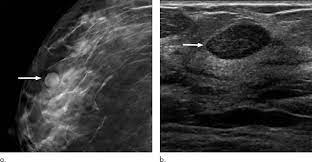

How Long Does A Mammogram Take Scanning And Results

How Long Does A Mammogram Take Scanning And Results from i0.wp.com